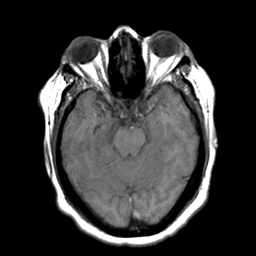

Cerebral hemorrhage, MR Study mr-t1 -- Slice #9

[Home][Help][Clinical] Slice 9